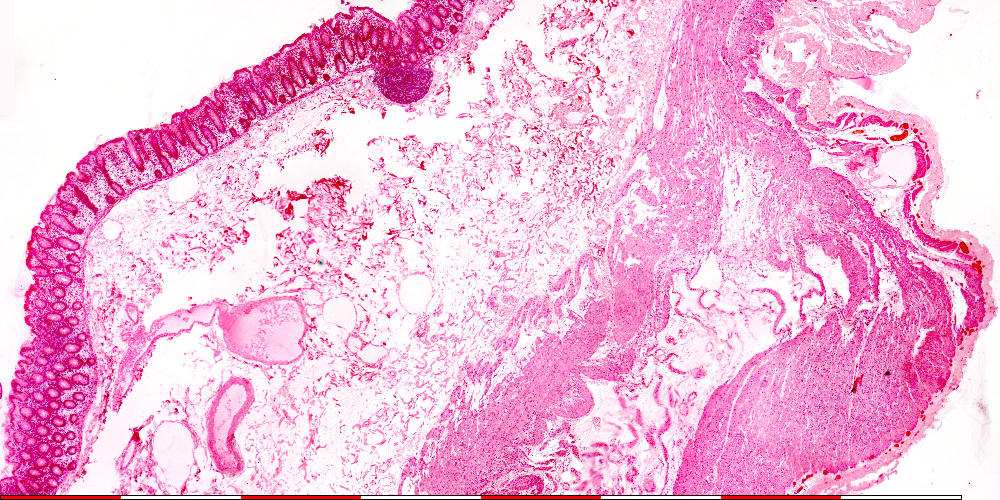

Kolon

Colon

© mei 2007 marius loots